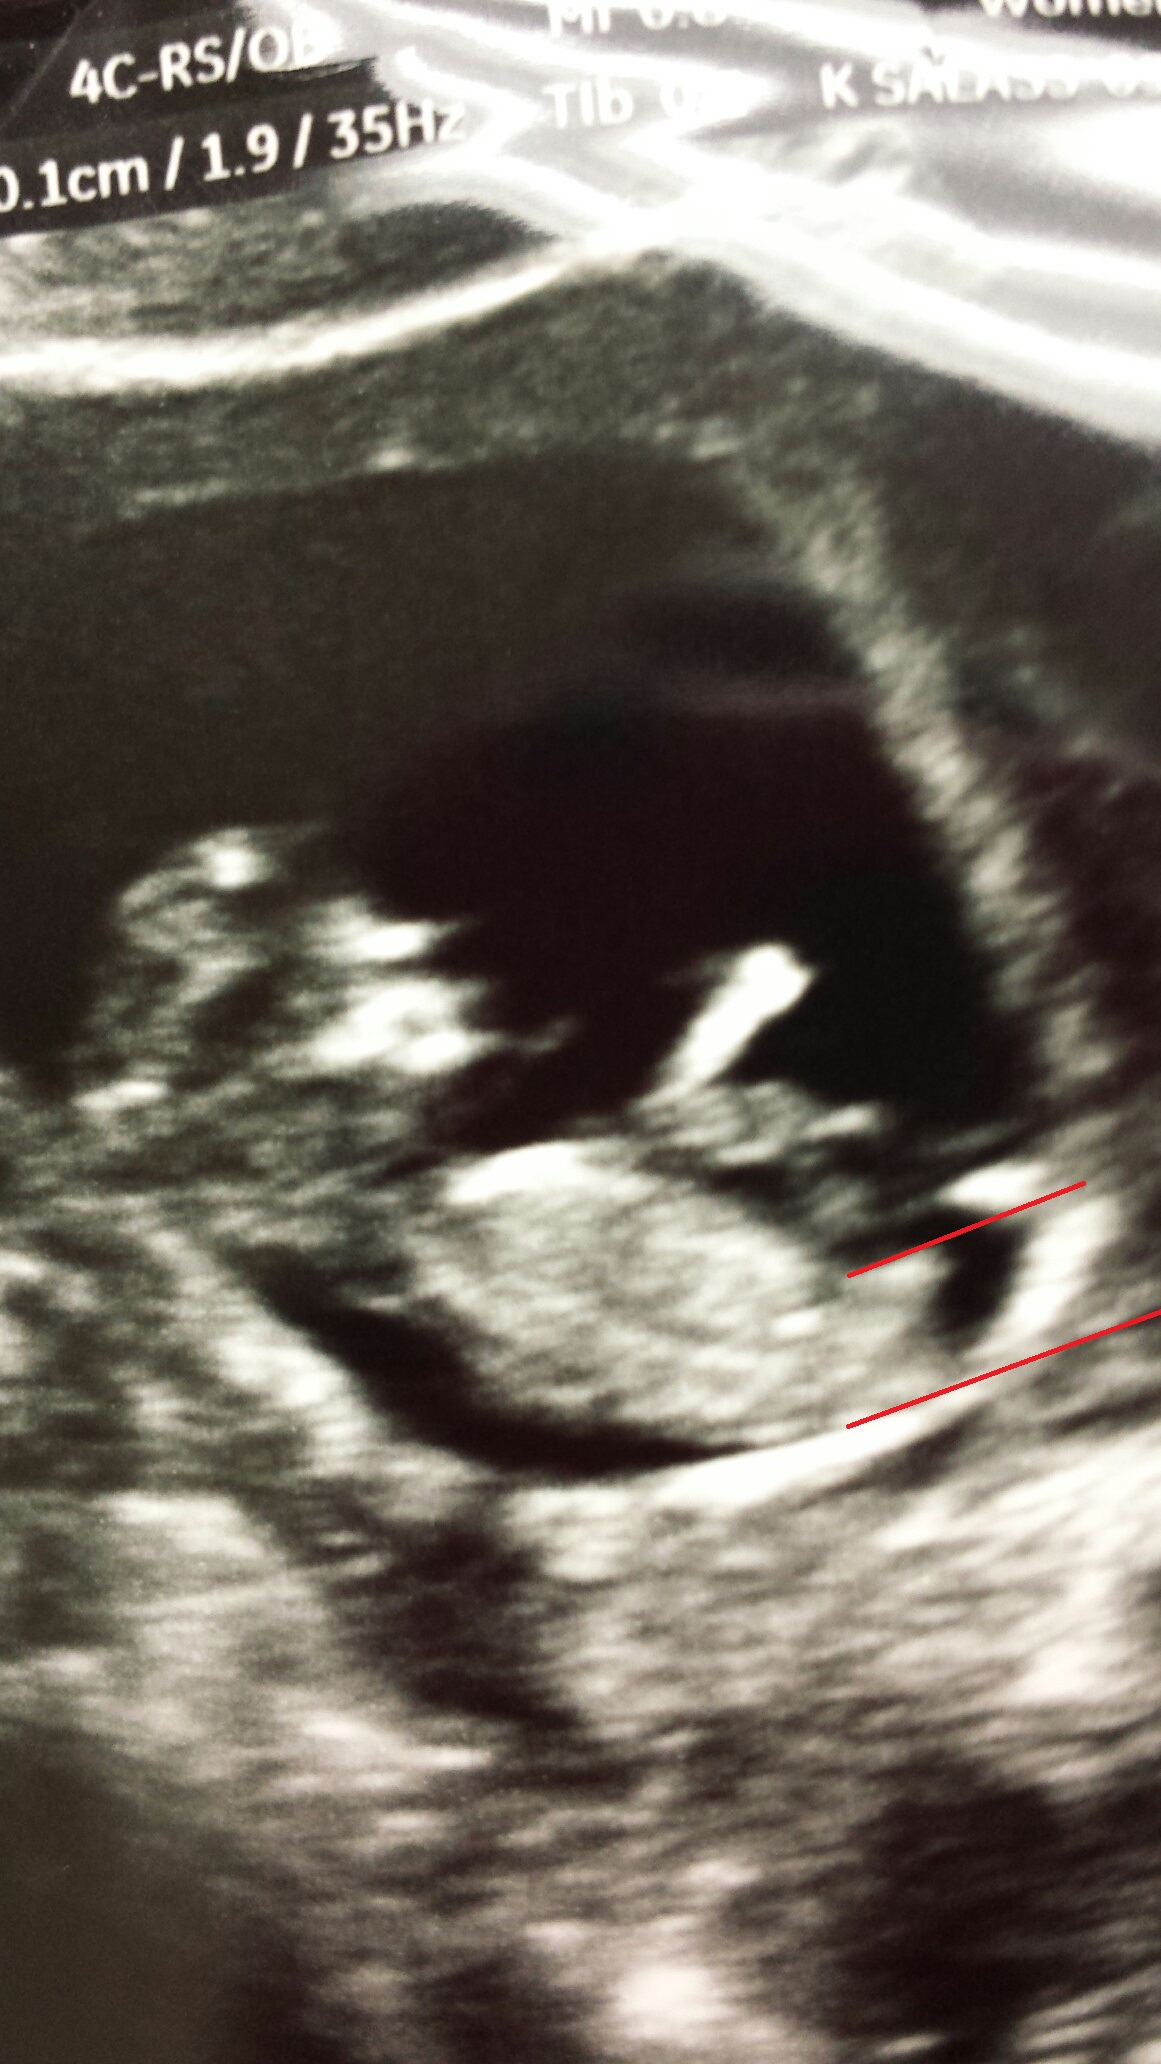

Here are the 2 pics marked and unmarkedAttachment 21201Attachment 21202

boy guess

Guessing girl

boy

I would be slightly swayed boy but wouldn't be suprises if you hear girl x

Leaning boy

Leaning girl

Id lean more boy. I see more of a rise in the making than a parallel.

Leaning boy, but what's the gestation?